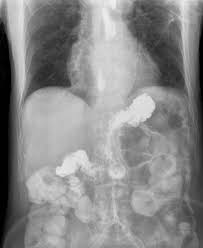

Progressive pain gets worse over time and often comes with other symptoms. Hypochlorhydria, or low stomach acid, is a commonly overlooked problem that is linked to other diseases like stomach cancer, asthma and rheumatoid arthritis. Discover 10 common low stomach acid symptoms at 10faq health and stay better informed to make healthy living decisions. Usually, by the time stomach cancer is diagnosed, the prognosis is poor. Many people have symptoms of gastroesophageal reflux disease, or gerd, often called acid reflux.

Hiatal Hernia Symptoms And Causes Mayo Clinic from www.mayoclinic.org Low stomach acid = low minerals = acidic blood. Low stomach acid eventually creates a vicious cycle: Low stomach acid = inability to absorb nutrients properly. Your problem is likely low stomach acid, not too much acid as the drug makers will try to convince you; The vicious cycle of low stomach acid affects your inner ecosystem too. If you have acid reflux symptoms or other digestive issues, chance are you have low stomach acid. These symptoms happen because your small intestine cannot absorb nutrients from food that has not been digested properly in the stomach. Many people have symptoms of gastroesophageal reflux disease, or gerd, often called acid reflux.

(while conventional medical doctors sometimes. Anything that is causing a chronic stress in our body from poor diet, bad. Usually, by the time stomach cancer is diagnosed, the prognosis is poor. And in terms of when to know if she can stop supplementing, i would base that on her symptoms. Learn the symptoms of low stomach acid. When stomach acid production is low, dysfunction throughout the digestive system can occur, leading to numerous symptoms and disease processes. The symptoms you experience with low stomach acid levels are related to disrupted digestion, poor nutrient absorption, and increased susceptibility to infection. Plus, two simple methods you can try at home. Let's take a look at some of the most common symptoms that result from having low stomach acid. This video shows how the esophagus works and how acid can. Keep in mind that some individuals may experience reactions on the. There are two specific ways in which poor digestion can affect the health of your digestive tract: In the case of low stomach acid, also called hypochlorhydria, some food will not be digested and, therefore, substantial amounts of nutrients in the food will not be released for.

Exercises and treatment depending on the severity of your gerd, there may be lower esophageal sphincter exercises that can help strengthen the muscle and alleviate symptoms. Your doctor will start with a history of your health and a physical exam and then will conduct a ph test or acidity test of your stomach. In the case of low stomach acid, also called hypochlorhydria, some food will not be digested and, therefore, substantial amounts of nutrients in the food will not be released for. Low stomach acid can be a big contributor to autoimmunity through gi inflammation and zinc deficiency that is often caused by low stomach acid. The symptoms you experience with low stomach acid levels are related to disrupted digestion, poor nutrient absorption, and increased susceptibility to infection. The vicious cycle of low stomach acid affects your inner ecosystem too. Low stomach acid prevents the stomach from breaking down bacteria and absorbing nutrients into the body. Low stomach acid = low minerals = acidic blood. Many people have symptoms of gastroesophageal reflux disease, or gerd, often called acid reflux. Low stomach acid can lead to more bad guys (pathogenic bacteria, candida and viruses) than good guys (healthy. Webmd looks at some of the causes of abdominal pain. It's a serious problem that needs to be investigated. After this food movement, fluid from the stomach rushes into your small intestine.

Now, hydrochloric acid is naturally created in your stomach. How does my stomach acid get low anyway? This fluid is a mixture of stomach acid and partially digested foods and beverages. Stomach acid declines with age, which is why many elderly. In the case of low stomach acid, also called hypochlorhydria, some food will not be digested and, therefore, substantial amounts of nutrients in the food will not be released for. Taking indigestion medication (antacids) may relieve the pain temporarily, but it'll keep coming back if the ulcer isn't treated. Anything that is causing a chronic stress in our body from poor diet, bad. Low stomach acid = inability to absorb nutrients properly. Symptoms of low stomach acid span a full spectrum of digestive tract related disorders. Low stomach acid can lead to more bad guys (pathogenic bacteria, candida and viruses) than good guys (healthy. He arrived at this conclusion after measuring the stomach ph of thousands of patients in his clinic. Low stomach acid can cause a feeling of fullness after eating, bloating and discomfort, and even lower your appetite (this is oftentimes the case in the elderly). Usually, by the time stomach cancer is diagnosed, the prognosis is poor.